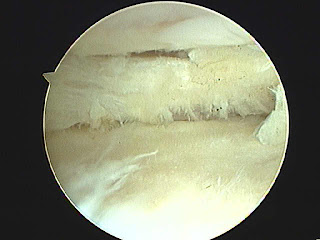

Tendinitis inferior de la rótula y reblandecimiento del cartílago.

El tratamiento médico, ejercicios específicos y esta configuración, podrán ayudar a mejorar la sintomatología.